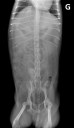

Archives de catégorie – Ils ont mangé quoi ?

• Ils ont mangé quoi ? (18)